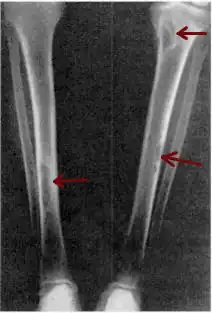

| Osteitis fibrosa cystica of the tibia. Arrows point to the brown tumors which are typically present in bones of people with OFC. | |

Osteitis fibrosa cystica (/ˌɒstiˈaɪtɪs faɪˈbroʊsə ˈsɪstɪkə/ OSS-tee-EYE-tis fy-BROH-sə SIS-tik-ə) is a skeletal disorder resulting in a loss of bone mass, a weakening of the bones as their calcified supporting structures are replaced with fibrous tissue (peritrabecular fibrosis), and the formation of cyst-like brown tumors in and around the bone. Osteitis fibrosis cystica (OFC), also known as osteitis fibrosa, osteodystrophia fibrosa, and von Recklinghausen's disease of bone (not to be confused with von Recklinghausen's disease, neurofibromatosis type I), is caused by hyperparathyroidism, which is a surplus of parathyroid hormone from over-active parathyroid glands. This surplus stimulates the activity of osteoclasts, cells that break down bone, in a process known as osteoclastic bone resorption. The hyperparathyroidism can be triggered by a parathyroid adenoma, hereditary factors, parathyroid carcinoma, or renal osteodystrophy. Osteoclastic bone resorption releases minerals, including calcium, from the bone into the bloodstream, causing both elevated blood calcium levels, and the structural changes which weaken the bone. The symptoms of the disease are the consequences of both the general softening of the bones and the excess calcium in the blood, and include bone fractures, kidney stones, nausea, moth-eaten appearance in the bones, appetite loss, and weight loss.

X-rays may also be used to diagnose the disease. Usually, these X-rays will show extremely thin bones, which are often bowed or fractured. However, such symptoms are also associated with other bone diseases, such as osteopenia or osteoporosis.[29] Generally, the first bones to show symptoms via X-ray are the fingers.[22] Furthermore, brown tumors, especially when manifested on facial bones, can be misdiagnosed as cancerous.[29] Radiographs distinctly show bone resorption and X-rays of the skull may depict an image often described as "ground glass" or "salt and pepper".[30][31] Dental X-rays may also be abnormal.[2]

Cysts may be lined by osteoclasts and sometimes blood pigments, which lend to the notion of "brown tumors." Such cysts can be identified with nuclear imaging combined with specific tracers, such as sestamibi.[3] Identification of muscular degeneration or lack of reflex can occur through clinical testing of deep tendon reflexes, or via photomotogram (an achilles tendon reflex test).[24][32]